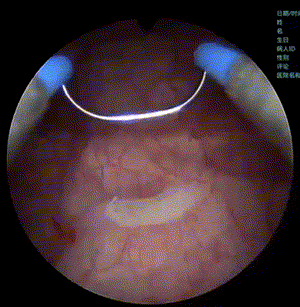

APL-1706202310月举行的国际泌尿外科学会年会(SIU)上以口头报告形式首次发布Ⅲ期临床试验数据,临床结果入选Late-Breaking AbstractLBA)。该研究证实了在中国患者中,APL-1706联合蓝光膀胱镜(BLCbluelight cystoscopy)在膀胱癌检测方面优于白光膀胱镜 (WLCwhite light cystoscopy),尤其是原位癌(CIScarcinoma in situ)的检出,并且其耐受性良好。

蓝光下可以有效提高CIS的检出率